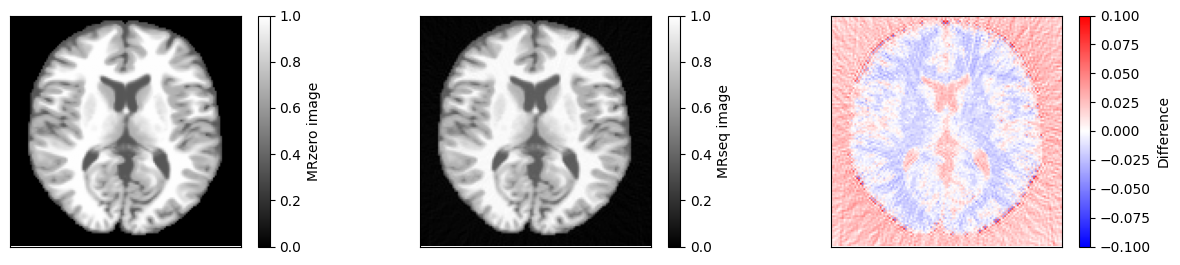

Compare to theoretical model#

We can now compare the result to a simulation using the idealized signal model for spoiled gradient echo sequences. First, we need to calculate \(T2^*\) using \(1/T2^* = 1/T2 + 1/T2'\).

fig, ax = plt.subplots(1, 3, figsize=(15, 3))

im = ax[0].imshow(idat_model, vmin=0, vmax=1, cmap='gray')

fig.colorbar(im, ax=ax[0], label='MRzero image')

im = ax[1].imshow(idat, vmin=0, vmax=1, cmap='gray')

fig.colorbar(im, ax=ax[1], label='MRseq image')

im = ax[2].imshow(idat - idat_model, cmap='bwr', vmin=-0.1, vmax=0.1)

fig.colorbar(im, ax=ax[2], label='Difference')

relative_error = np.sum(np.abs(idat - idat_model)) / np.sum(np.abs(idat_model))

print(f'Relative error {relative_error}')

assert relative_error < 0.05

Relative error 0.03551841384450442